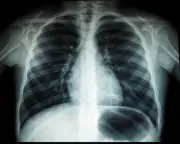

Kementerian Kesihatan Kurangkan Masa Tunggu Pembedahan Jantung

Kementerian Kesihatan Malaysia melaksanakan pelbagai langkah termasuk penambahbaikan infrastruktur dan latihan pakar untuk mengurangkan masa tunggu pesakit jantung yang memerlukan rawatan kritikal di seluruh negara.